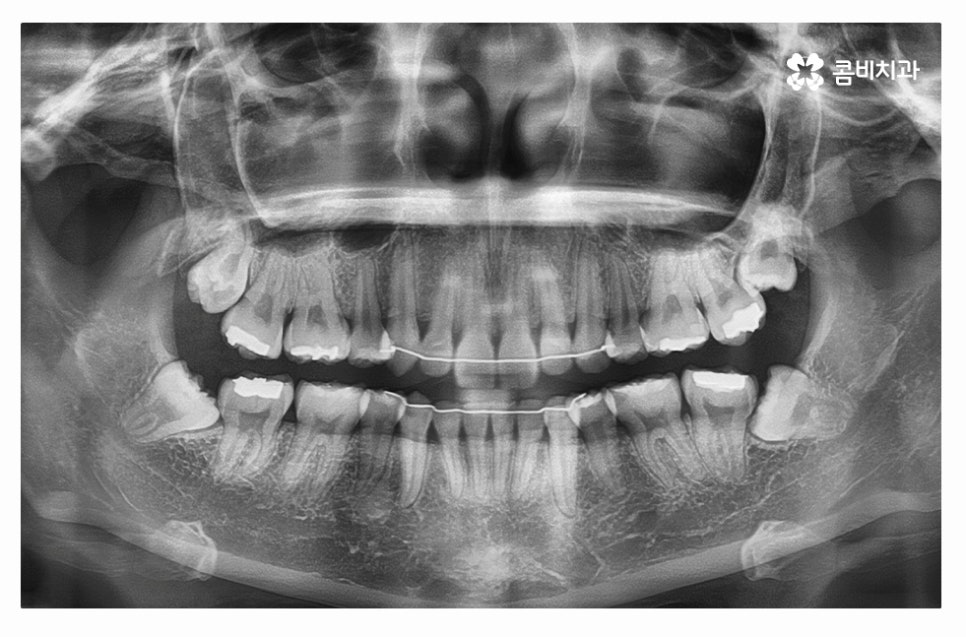

누운사랑니발치 사례를 보면서 설명을 듣는다면 더욱 이해가

잘 되실 텐데 위 사진처럼 사랑니가 어금니 방향으로

자라고 있는 경우에는 치아 사이 충치를 유발하거나

잇몸질환의 원인이 될 수도 있는데요.